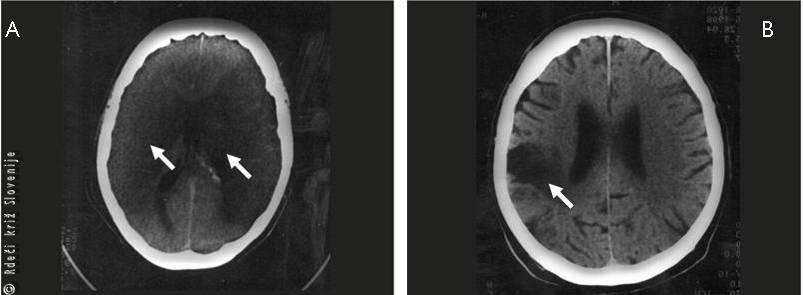

Slika 3

Globinsko slikanje ishemične možganske kapi zaradi zapore možganske žile.

A – Obsežna, obojestranska možganska kap, ki hitro privede do izgube zavesti.

B – Manj obsežna ishemična možganska kap, brez izgube zavesti, vendar s prizadetostjo gibanja ene polovice telesa ter izgube daru govora.